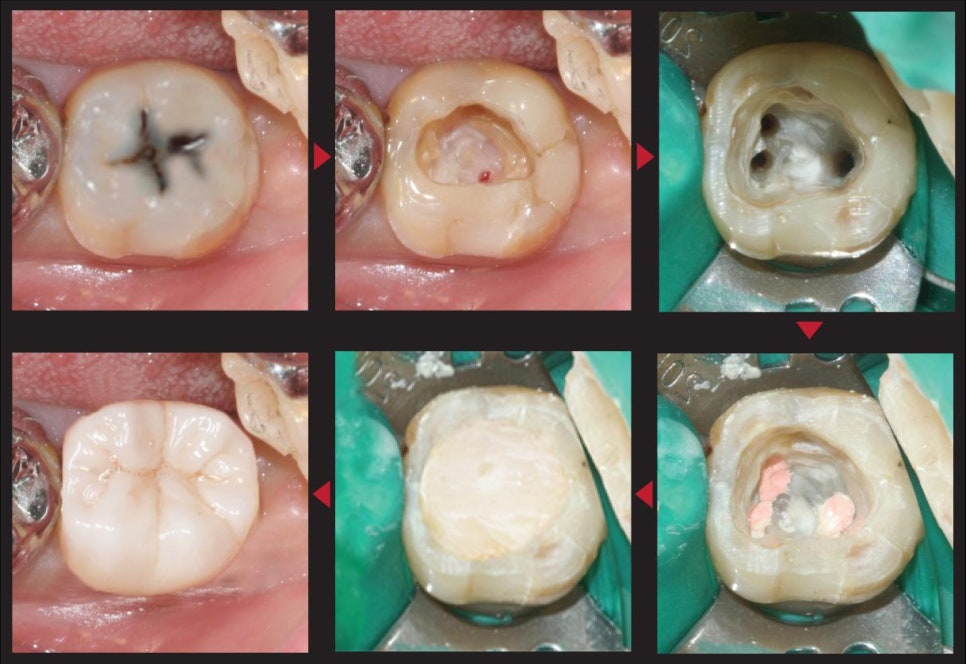

🦷 신경치료 (근관치료) 과정 – 미세현미경 사용

외상으로 치아가 크게 손상된 경우,

치아 내부 신경(치수)에 손상이 발생할 수 있기 때문에

신경치료가 필요합니다

손상된 치아 내부의 감염된 조직 제거

치근관(신경이 지나가는 길)을 소독 및 세척

세균이 다시 침투하지 않도록 밀봉

치아가 깨어진 부위를 보강할 수 있도록 코어(기둥) 형성

이렇게 치아 내부를 안전하게 정리하고 구조를 보강한 뒤,

기능과 심미성을 함께 고려한 보철 치료를 이어갔습니다

신경치료 과정